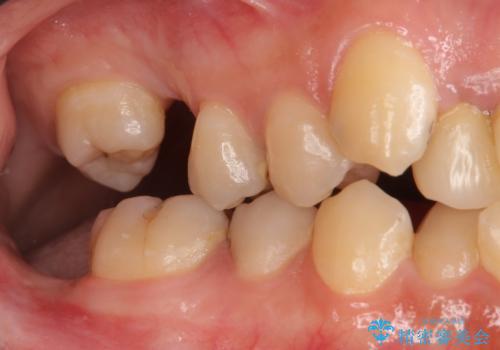

虫歯が多数、また奥歯も欠損してしまっていました。

左下の親知らず、左上の小臼歯が残根状態で一本抜いたほかは抜かずに矯正しました。